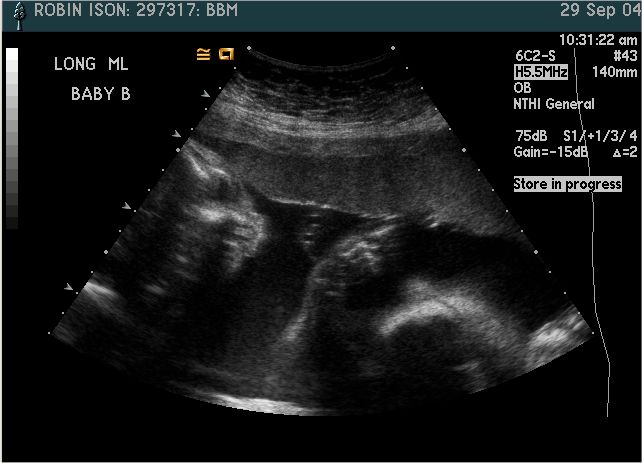

Baby B

Pictures from Ultrasound at 26 weeks.